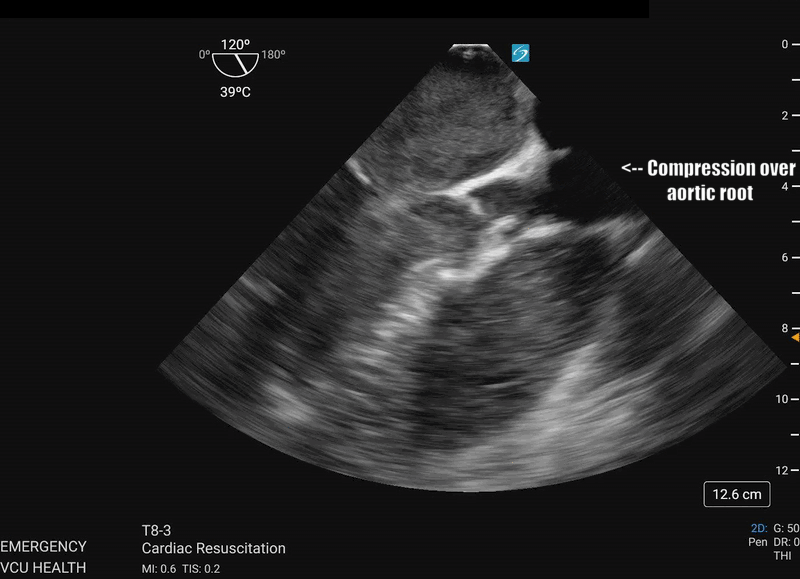

Most importantly for the resuscitationist, the ME-LAX view is used to evaluate the quality of CPR and hand placement for chest compressions; so it should be obtained during initiation of CPR and even when changing CPR providers if possible. Optimal chest compressions should result in vigorous LV squeeze with near concurrent aortic valve opening (Figure 2). Incorrect compressions, usually too high on the chest wall, will result in LV outflow obstruction and ineffective CPR (Figure 3). This can be seen on the ME-LAX view as squeeze over the AV itself, narrowing of the aortic outflow tract, absence of LV compression and/or absence of aortic valve opening during compressions. Signs of ineffective CPR should prompt adjustments in compression location and/or depth and subsequent re-evaluation for effectiveness.2

Figure 3: ME-LAX view during CPR (slowed to 50% speed) showing complete compression of the aortic root during CPR

The team performs the ME-LAX view to assess the left ventricle, mitral valve and left ventricular outflow tract in real time. The image shows that the LVOT is not opening well due to improper hand placement during compressions. The team recommended moving the compressors’ hands slightly lower on the sternum and near the xiphoid process to increase the force applied to the left ventricle and reduce the force on the LVOT. After the repositioning, the LV was noted to be squeezing more vigorously with concurrent AV opening with each compression. This adjustment improved the cardiac output and after a few more rounds of adjusted CPR and continued ACLS, ROSC was achieved